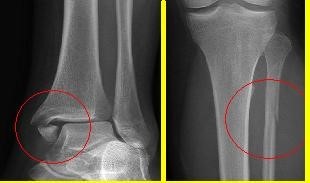

What is this?

Maisonneuve fracture